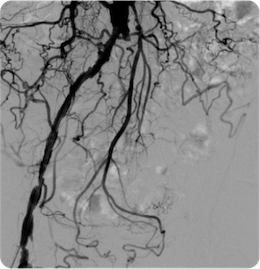

治療前

治療後

血管造影

左腸骨動脈が完全閉塞しており、左下肢の冷感、痛みを認めました。ステントを留置しいずれの症状も消失しています。